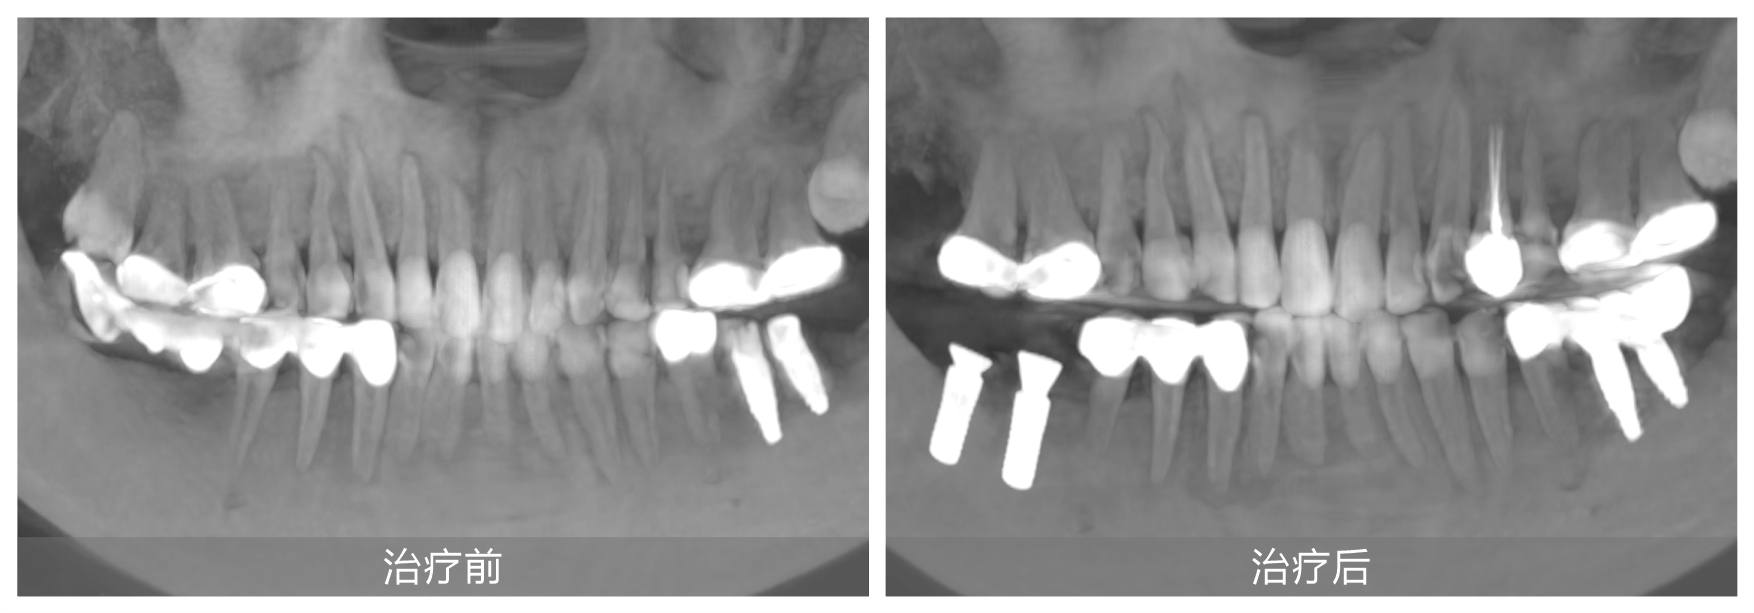

她自小牙齿不好,早年正牙过程中不幸遭遇正畸片切不当导致下颌右侧两颗磨牙严重受损,之后未经正规处理直接拔牙,造成重要磨牙缺失,严重影响咀嚼功能。随后原治疗机构采用倾斜智齿制作了不良烤瓷长桥修复,导致前磨牙牙髓坏死造成根尖炎。雪上加霜的是,五年前又被某口腔机构蹩脚医生把上颌两侧磨牙做了不必要的牙冠,之后下颌左侧两颗磨牙也因种植体位置不正导致牙冠频繁脱落,种植体也有折断风险。

果然,徐会医生不负所托轻松完成了刘女士下颌左侧的牙冠修复。并对其他牙齿问题提出了一套综合治疗方案:先拆除不良修复体,拔除下颌右侧的倾斜智齿,然后在缺牙处植入两颗种植牙,并对前磨牙实施根管治疗。这一方案更加微创,也更加经济和高效。